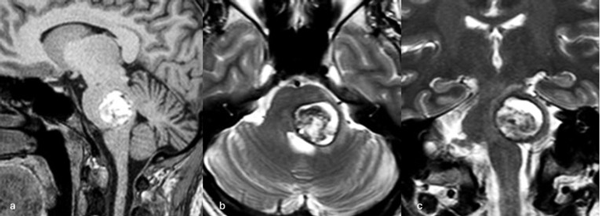

Figura 9. RM preoperatoria de encéfalo. Se evidencia una lesión única intraaxial bulbotrigonal izquierda, que contacta la mitad inferior del piso del cuarto ventrículo, hiperintensa en T1 y T2, con vacíos de flujo que impresionan provenir de una malformación del desarrollo venoso, lo que sugiere una malformación cavernomatosa. A) Imagen en corte sagital ponderada en T1 posterior a la administración de gadolinio. B y C) Imágenes en corte axial ponderadas en T1 y T2, respectivamente.